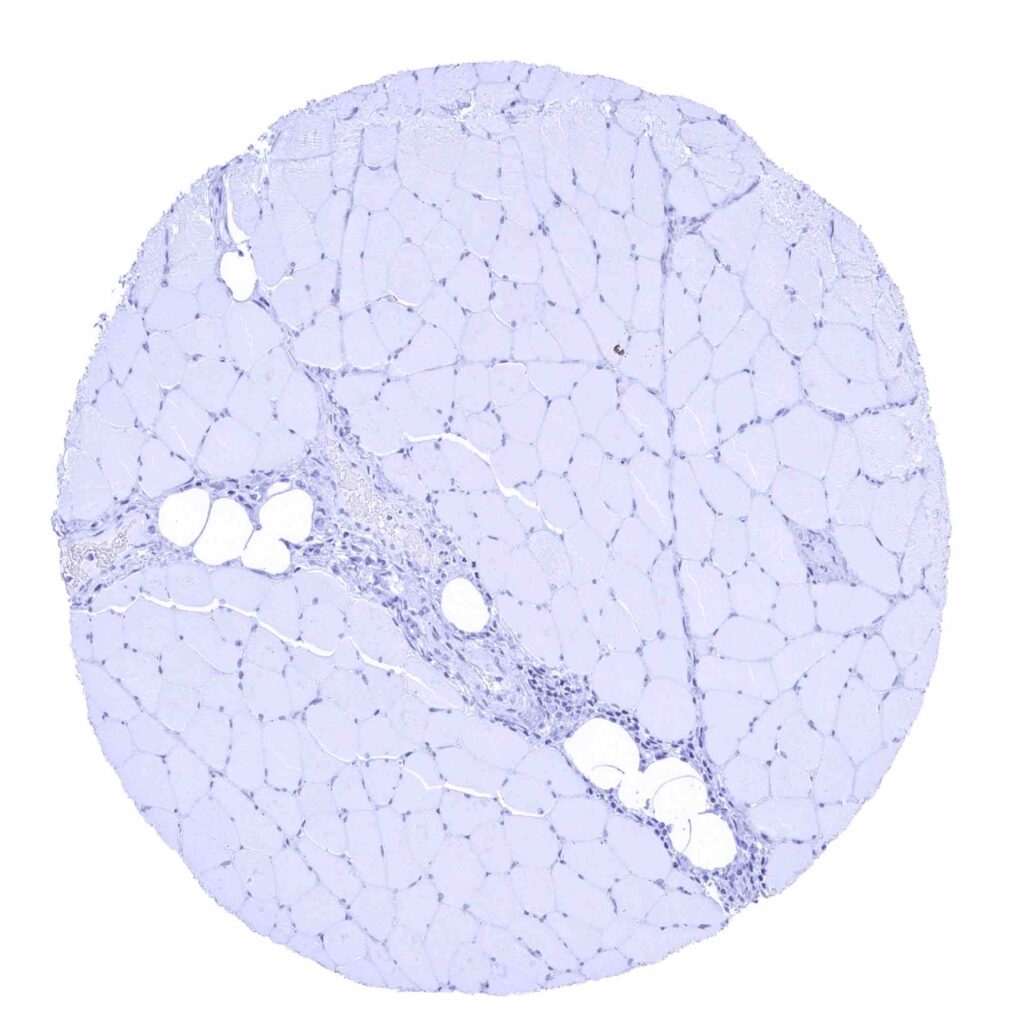

Fat

Skeletal muscle